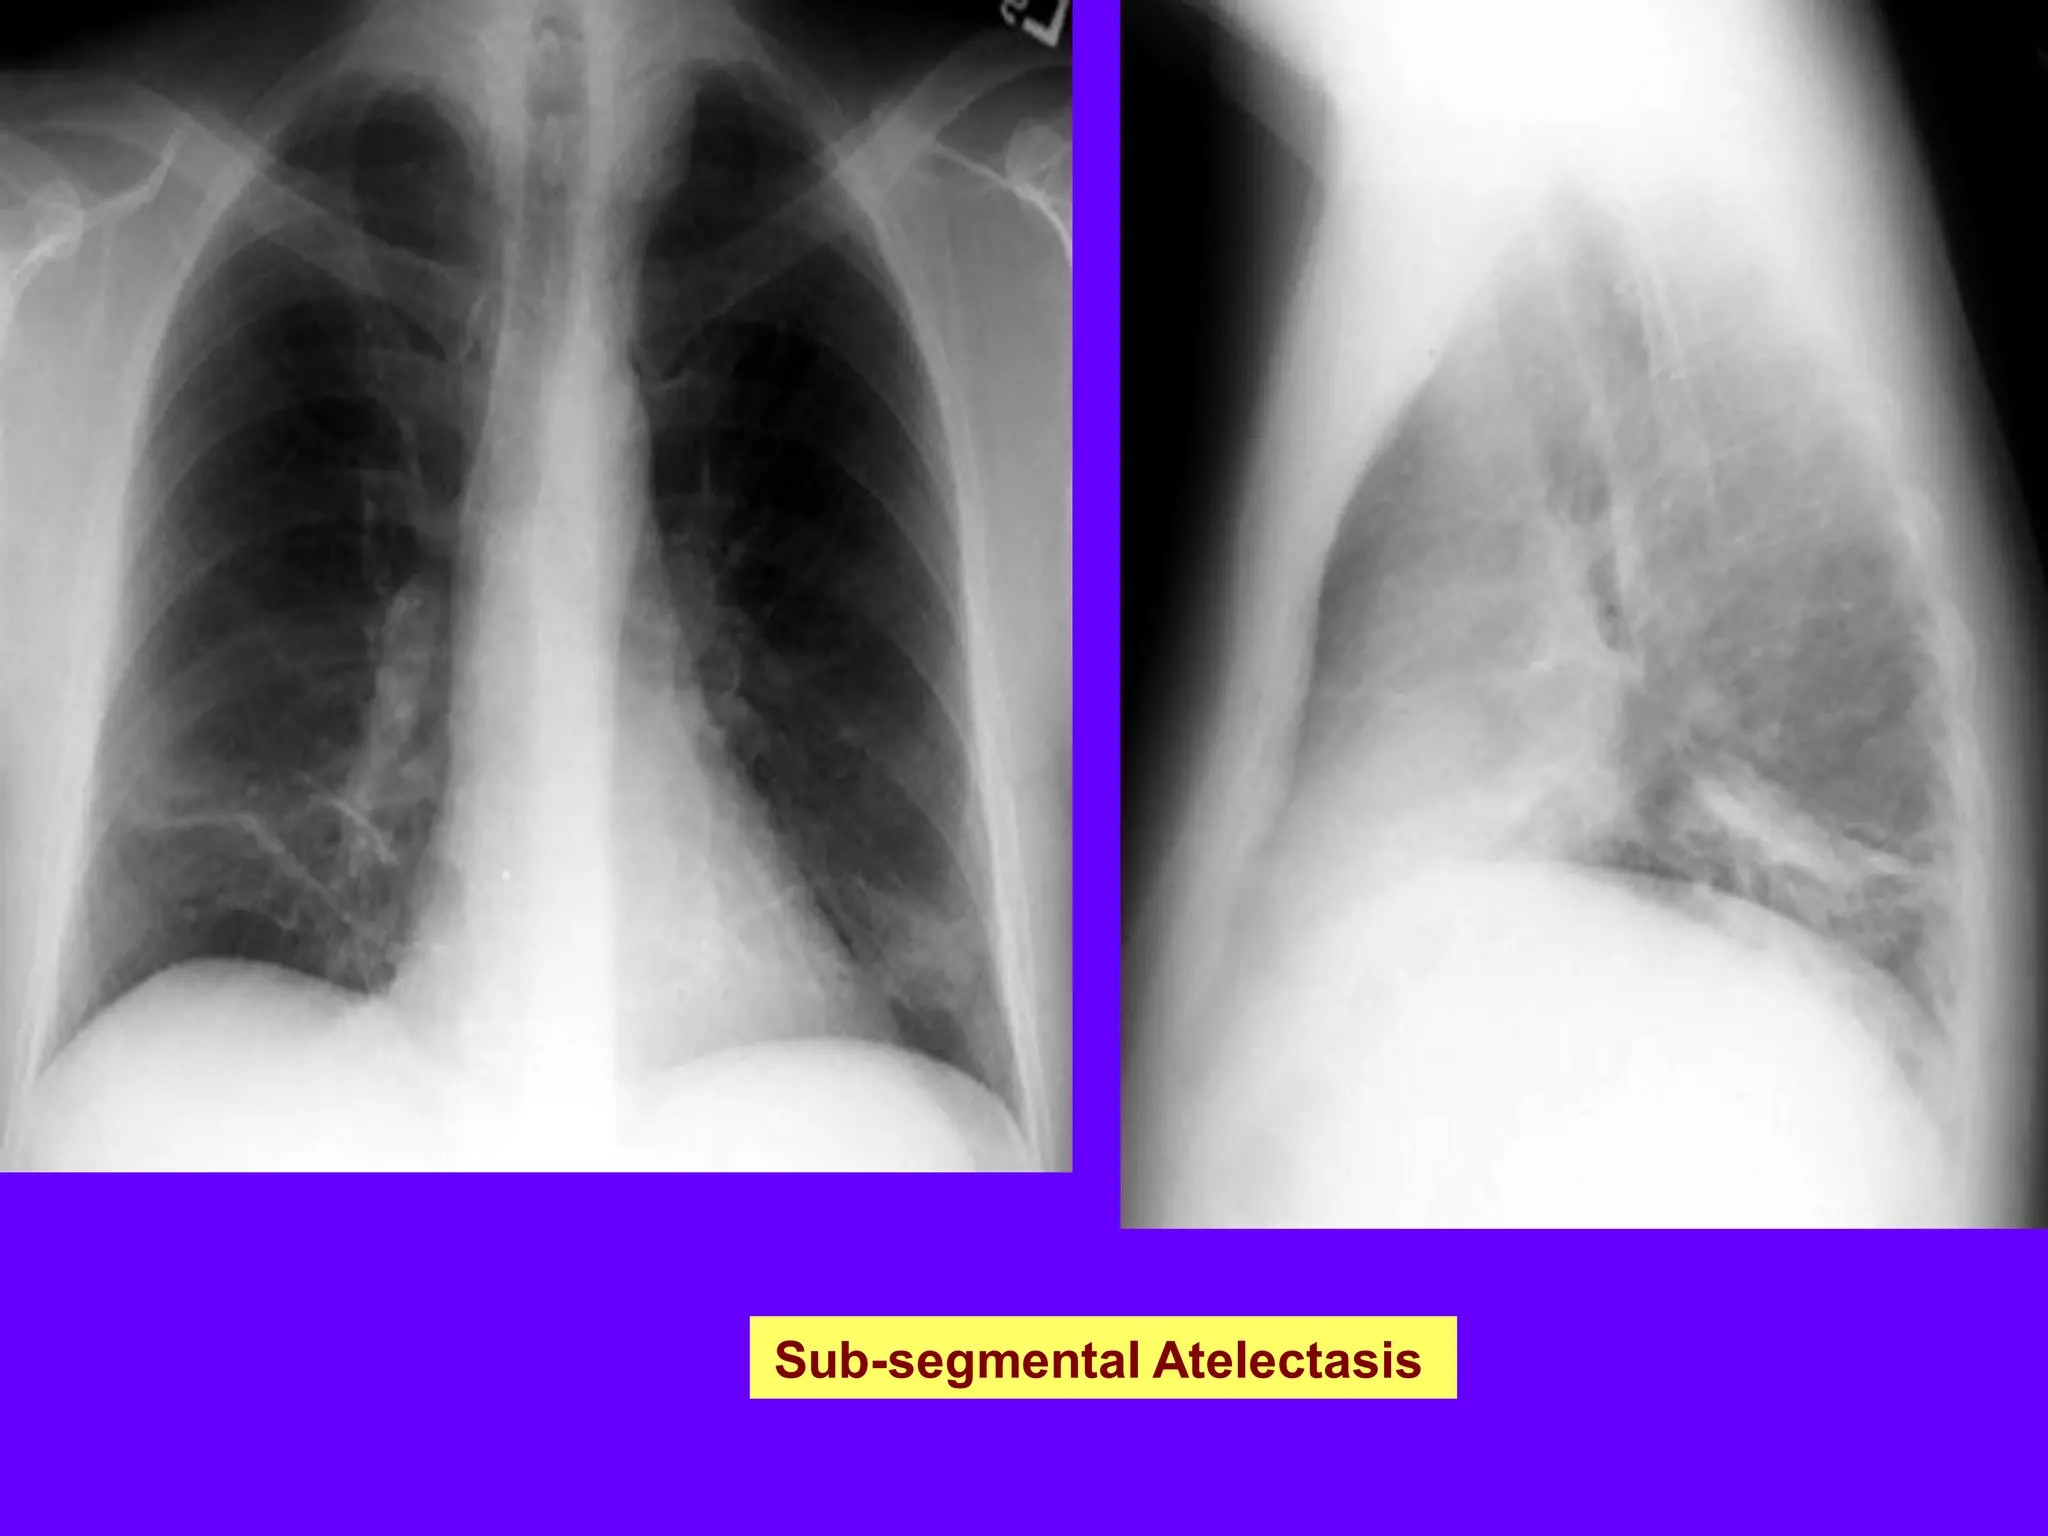

Sub-segmental Atelectasis

Atelectasis

Reduced volume is seen, accompanied by

increased opacity (chest radiograph) or

attenuation (CT scan) in the affected

part of the lung . Atelectasis is often

associated with abnormal displacement of

fissures,

bronchi,

vessels,diaphragm,

heart, or mediastinum .The distribution can

be lobar, segmental, or subsegmental.

Atelectasis is often qualified by descriptors

such as linear,discoid, or platelike.